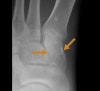

cf) 설상골 골절(Cuneiform fracture)

무거운 물체가 발등에 떨어져서 일어나는 직접 골절입니다.

**X-ray :**설상골 골절(Cuneiform fracture)